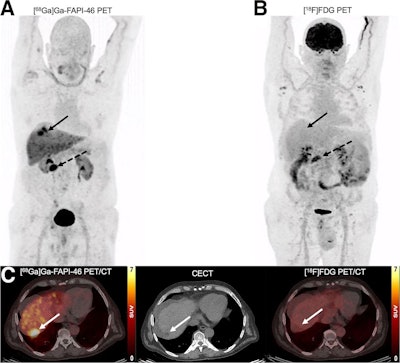

A 65-y-old man with HCC and liver cirrhosis confirmed by MRI. Ga-68 FAPI-46 PET/CT demonstrates increased focal uptake (SUVmax, 13.26, and TBRmax, 2.89) in liver, whereas F-18 FDG-PET/CT scans showed non–F-18 FDG-avid lesion (SUVmax, 3.24, and TBRmax, 1.43), indicated by solid arrows. Additionally, histologically proven adenocarcinoma in colon transversum was identified as pathologic with Ga-68 FAPI-46 alone (dashed arrows).A 65-y-old man with HCC and liver cirrhosis confirmed by MRI. Ga-68 FAPI-46 PET/CT demonstrates increased focal uptake (SUVmax, 13.26, and TBRmax, 2.89) in liver, whereas F-18 FDG-PET/CT scans showed non–F-18 FDG-avid lesion (SUVmax, 3.24, and TBRmax, 1.43), indicated by solid arrows. Additionally, histologically proven adenocarcinoma in colon transversum was identified as pathologic with Ga-68 FAPI-46 alone (dashed arrows). Journal of Nuclear MedicineAccording to the results, on the basis of visual analysis, 44 patients showed elevated Ga-68 FAPI-46 uptake (sensitivity, 100%; specificity, 94%), whereas 32 patients showed F-18 FDG-avid lesions (sensitivity, 70%; specificity, 88%). In addition, 50 (90.9%) benign liver lesions in 14 patients (87.5%) showed negligible uptake on both PET scans, and one (1.8%) benign liver lesion in one patient showed increased F-18 FDG uptake alone. Lastly, Ga-68 FAPI-46 PET/CT revealed 10 extrahepatic primary tumors versus three on F-18 FDG PET/CT, the researchers reported.